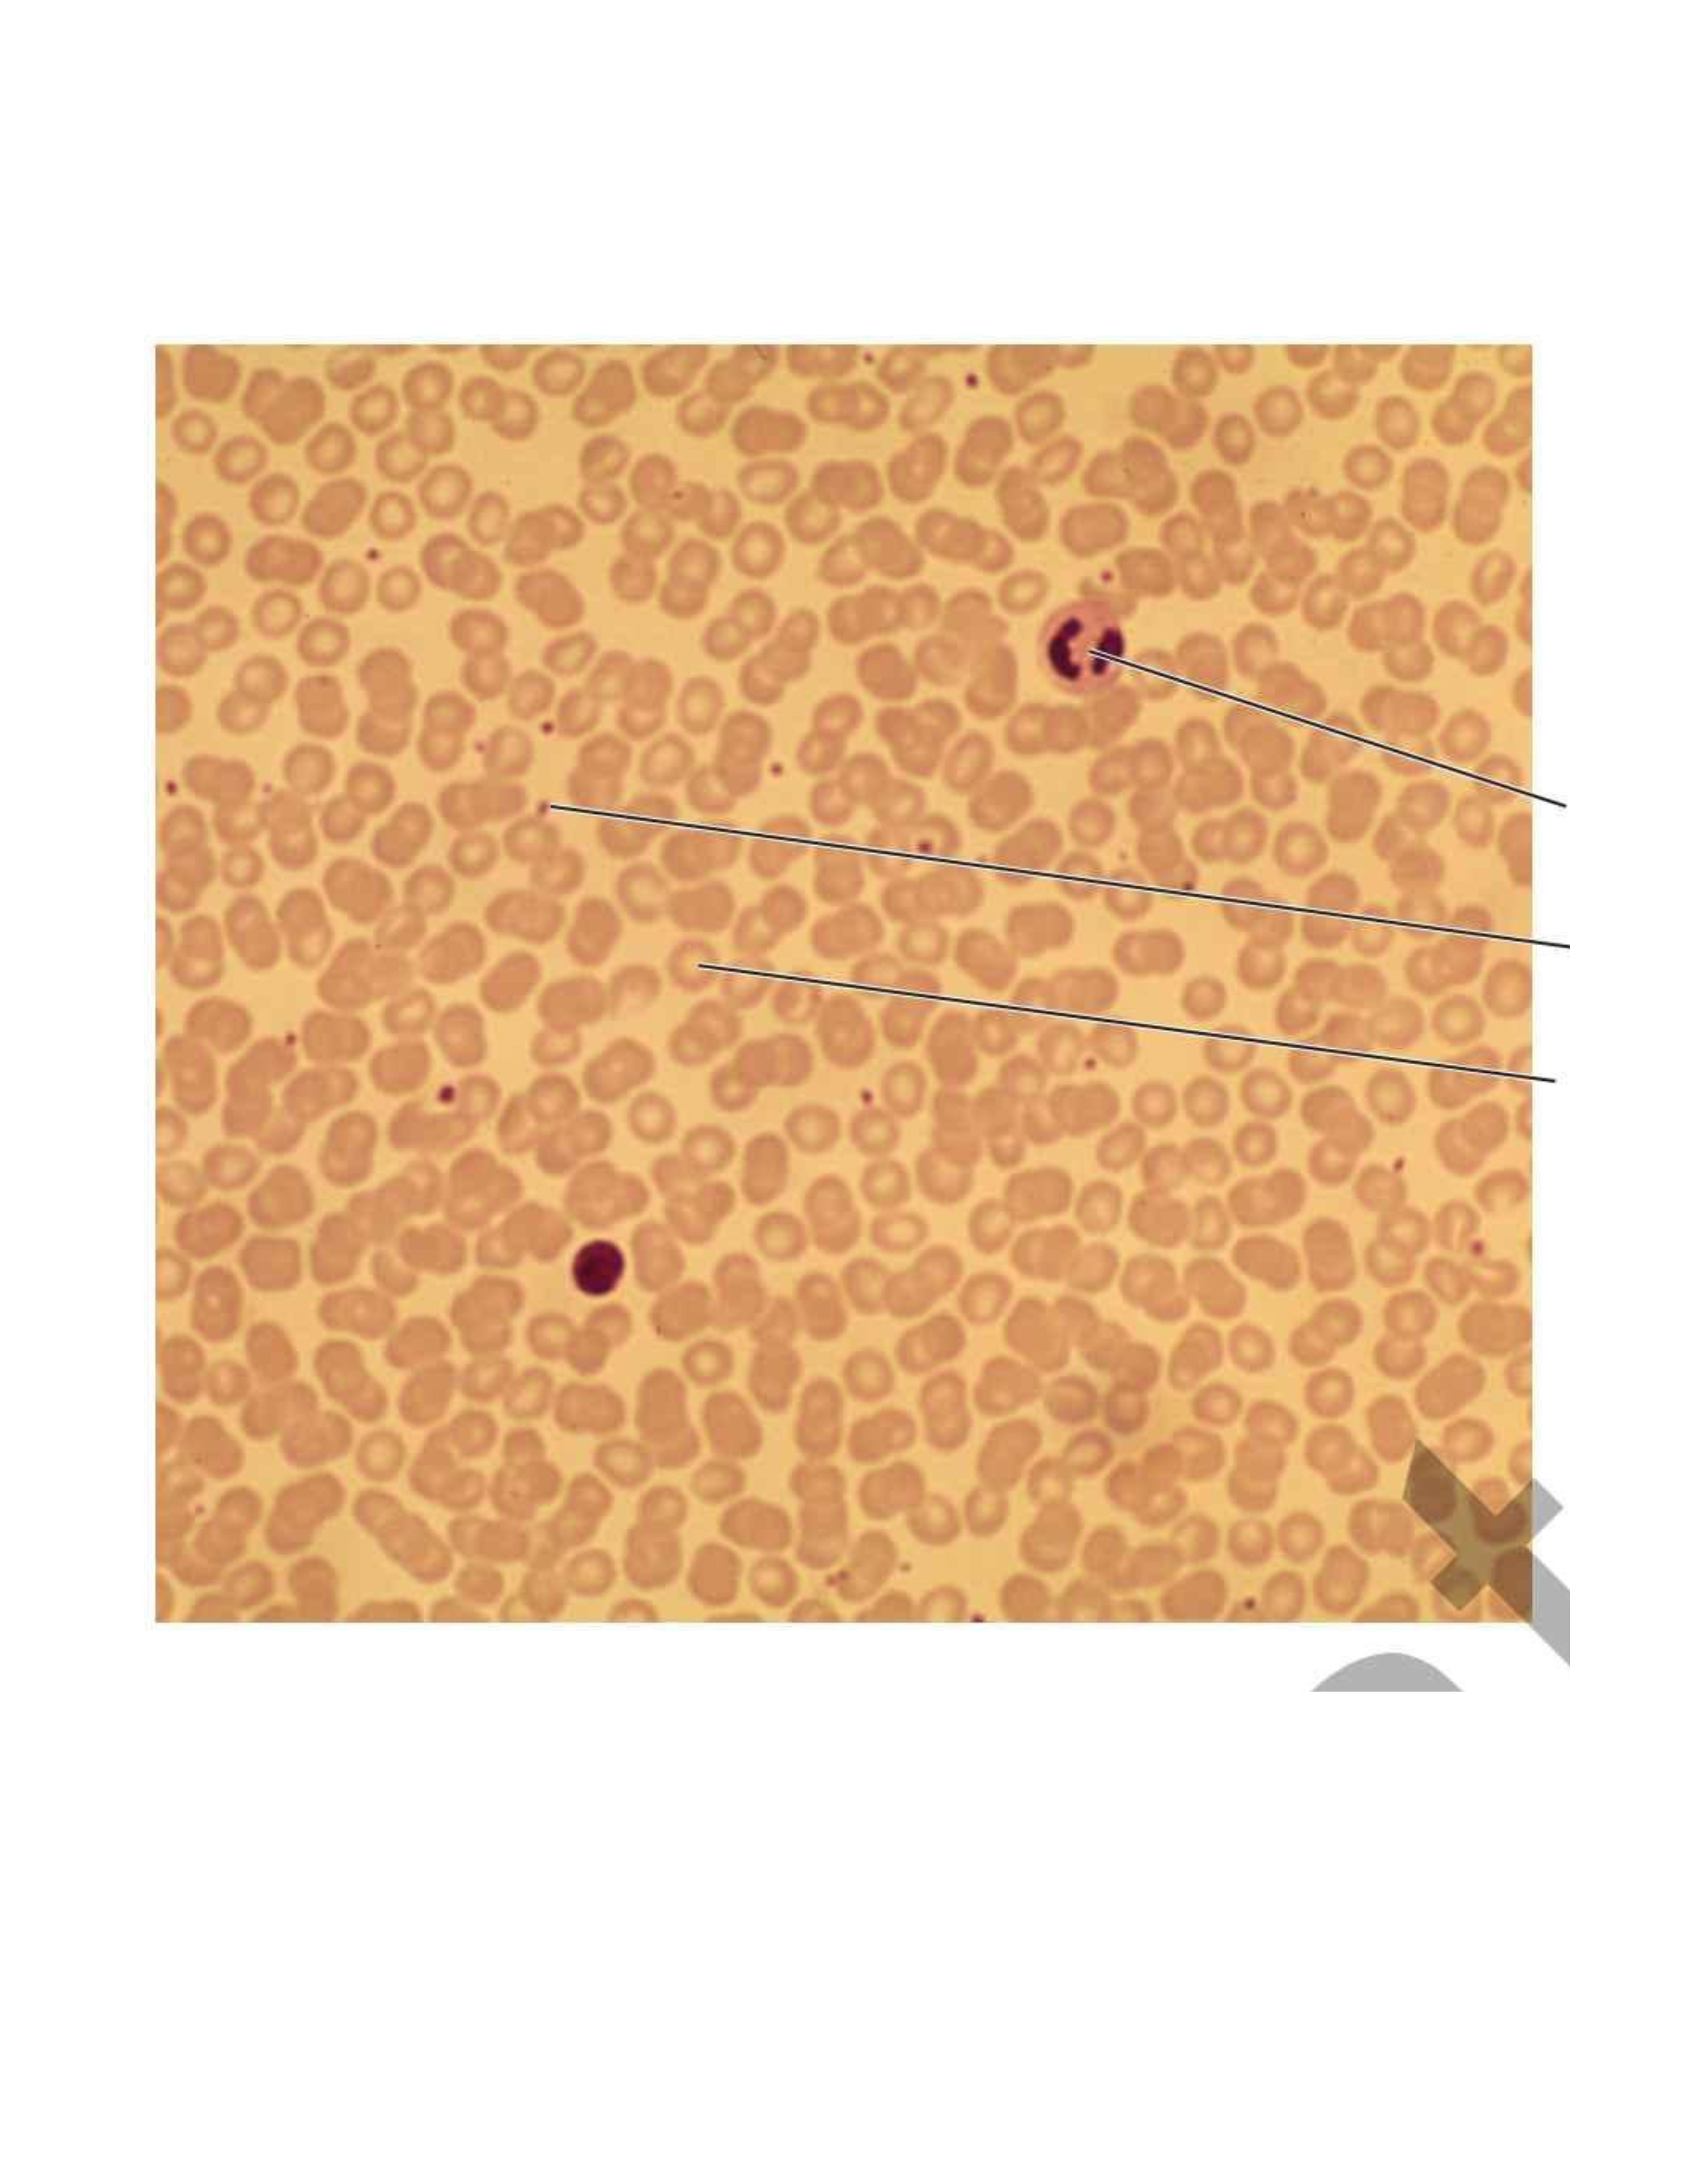

Blood

Function: Transports

Location: Blood vessels